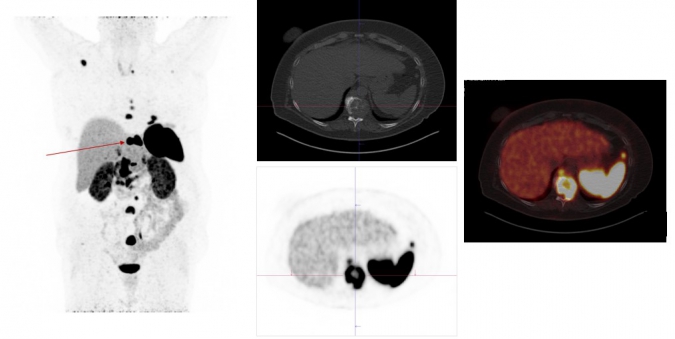

Exemplary case study on Ga-68-DOTANOC-PET/CT diagnostics: